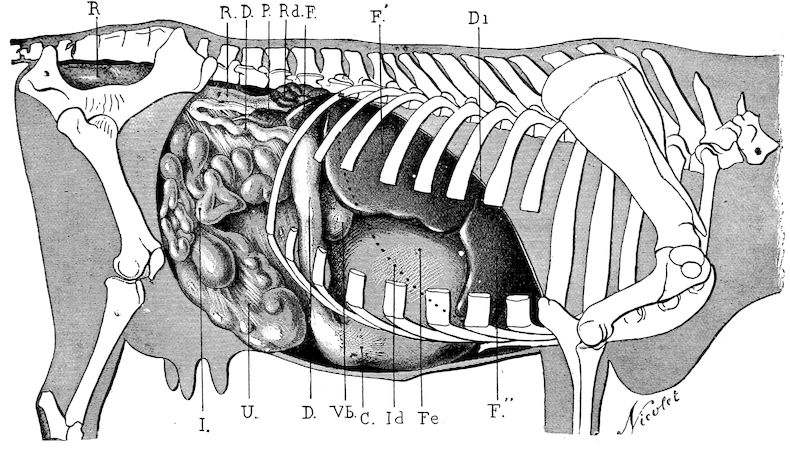

| Diseases of the stomach | 169 | |||

| Indigestion | 170 | |||

| Gaseous indigestion | 170 | |||

| x | Impaction of the rumen—Indigestion as a result of over-eating | 175 | ||

| Impaction of the omasum (third stomach) | 179 | |||

| Abomasal indigestion | 182 | |||